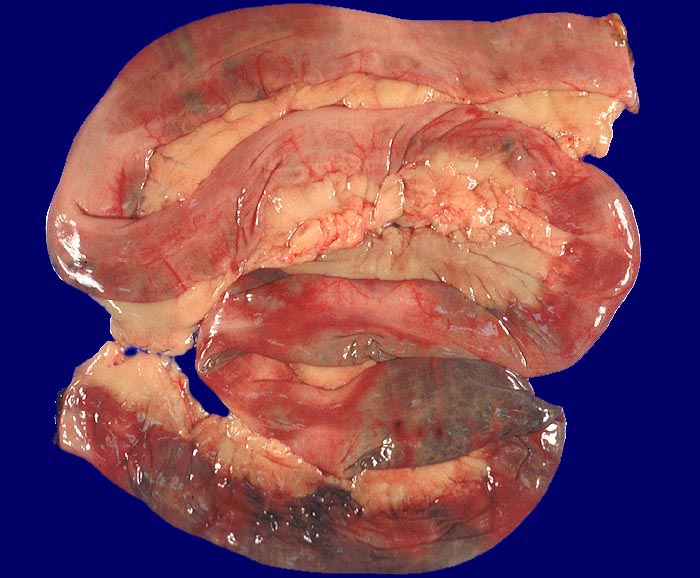

Mesenterialinfarkt

vaskulär / Durchblutungsstörung

Dünndarm

Makroskopie

Pathologischer Befund